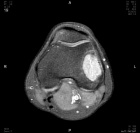

Patient is a 20 y/o male with a history of L. knee GCT s/p excision 11 months ago.

He presents w/ increasing L. knee pain; PMH: GCT; PE L. knee with no effusion + tenderness to palpation over lat. fem. condyle; + tenderness w/ PROM 0-95